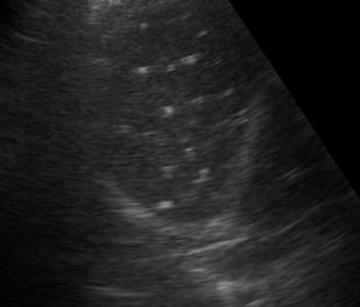

一般筛查首选超声检查,典型的特征是肝实质内斑点状、团块状强回声,无肝内外胆管扩张、无伴行肝静脉扩张,多为单发,肝右叶多见于肝左叶。